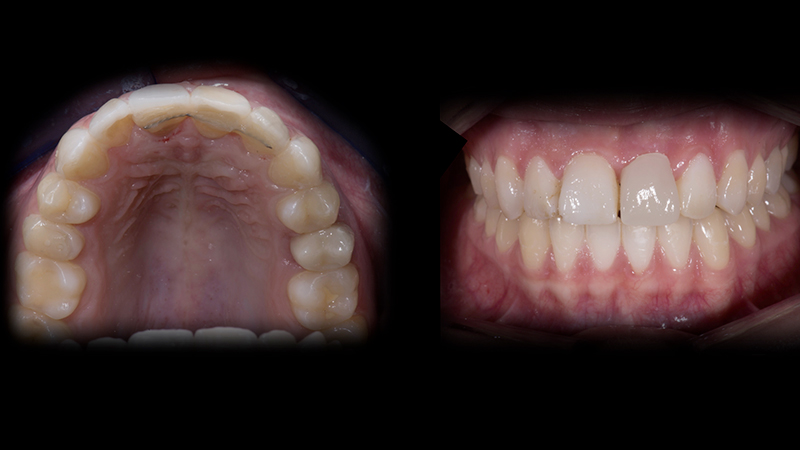

Terza fase

Il caso è stato finalizzato protesicamente seguendo un metodo digitale "chairside".

Grazie alla funzione "Copia Biogenerica" del software protesico, è possibile copiare la morfologia del mock-up precedentemente incollato e della corona provvisoria avvitata all'impianto. Condivideremo con il software di progettazione le forme testate per creare i restauri protesici definitivi.

1. Impronte definitive digitali. Ho eseguito con lo scanner intraorale la "Biocopia" dei denti anteriori e copiato la posizione delle papille e del margine gengivale, creando la "Maschera gengivale", condividendo contemporaneamente le informazioni morfologiche dei tessuti molli con il software di progettazione CEREC che creerà i dispositivi protesici finali (Fig. 17, Fig. 18a, Fig. 18b).

2. Preparazione dei denti anteriori. Nel piano di trattamento avevo previsto la realizzazione di 5 faccette da 1.3 a 2.3, ad eccezione della 2.1, su cui era prevista una corona da avvitare all'impianto (Fig. 19).

3. Impronta definitiva dei denti preparati. L'arcata preparata è scansionata con lo scanner intraorale (Fig. 20).

4. Sviluppo dei modelli master e progettazione digitale. Completata la fase di impronta, il software progetta i denti protesici definitivi. Per iniziare, traccio la "Linea di base" sul profilo dei tessuti molli, evidenziando l'area entro la quale il software rileverà e creerà una corona protesica con un profilo di emergenza adeguato a supportare le papille e il margine gengivale condizionati. Si traccia poi la linea di finitura della preparazione ed in seguito, la "Linea di copiatura", copiando il mock-up. Con queste informazioni, il software creerà i denti protesici definitivi (Fig. 21a, Fig. 21b, Fig. 21c).

5. Scelta del materiale e fresatura dei denti protesici. La scelta del materiale è un punto importante. La mia prima scelta sono le ceramiche feldspatiche, permettono di ottenere risultati molto simili alle caratteristiche estetiche dei denti naturali. Nel caso in cui sia necessario avere denti protesici con uno spessore molto sottile (0,2-0,3 mm), meglio scegliere una ceramica ibrida con una percentuale variabile di resina che conferisce maggiore elasticità, evita fratture durante la fresatura e ottiene margini precisi (Fig. 22).

6. Finalizzazione dei denti protesici. Questo punto è molto importante, definirà l'aspetto finale dei denti protesici. L'obiettivo a cui mirare non è creare “specchi" che riflettano la luce in modo uniforme, ma la creazione di una texture superficiale che rifletta la luce in modo diverso, conferendo un aspetto più naturale (Fig. 23b).

7. Cementazione adesiva. Questa ultima fase, se non gestita correttamente, potrebbe vanificare il risultato finale dal punto di vista estetico e funzionale. Gli aspetti principali da considerare per una ottimale stabilità dei dispositivi protesici nel tempo dopo la loro cementazione sono i seguenti: isolamento del sito operatorio con diga di gomma; preparazione conservativa; valutazione del colore finale.

Aspetto dei tessuti molli dopo la rimozione del provvisorio

Fig. 17 - Aspetto dei tessuti molli dopo la rimozione del provvisorio.

Impronta digitale dei tessuti molli

Fig. 18a - Impronta digitale dei tessuti molli "Maschera gengivale".

Copia Biogenerica del mock-up e del provvisorio avvitato

Fig. 18b - "Copia Biogenerica" del mock-up e del provvisorio avvitato.

Risultato finale

Fig. 24d - Risultato finale.

Risultato finale complessivo

Fig. 24e - Risultato estetico finale.